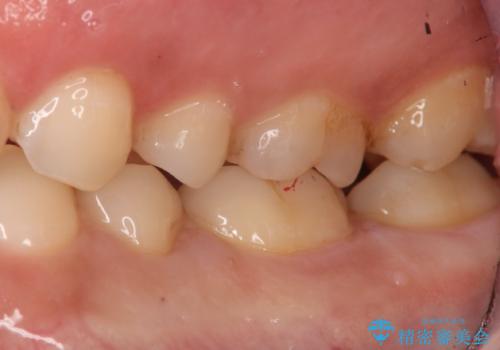

保険の材料と比較して、セラミックは劣化しにくく審美性も高い材料です。

自費の治療を希望されたため切削量・形態を考慮し、セラミックインレーでの治療を計画しました。

- 77000(税込)費用は治療当時の料金となります